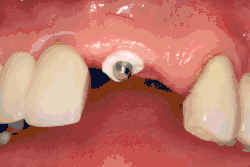

Формирователь десны (опора для заживления) прикрепляется к креплению имплантата, а лоскут десны накладывается на заживляющий абатмент.

Восстановление мягких тканей

Когда слизистая оболочка отсутствует, в область может быть трансплантирован свободный десневой трансплантат мягких тканей.

Когда металл имплантата становится видимым, можно использовать трансплантат соединительной ткани для улучшения высоты слизистой оболочки.